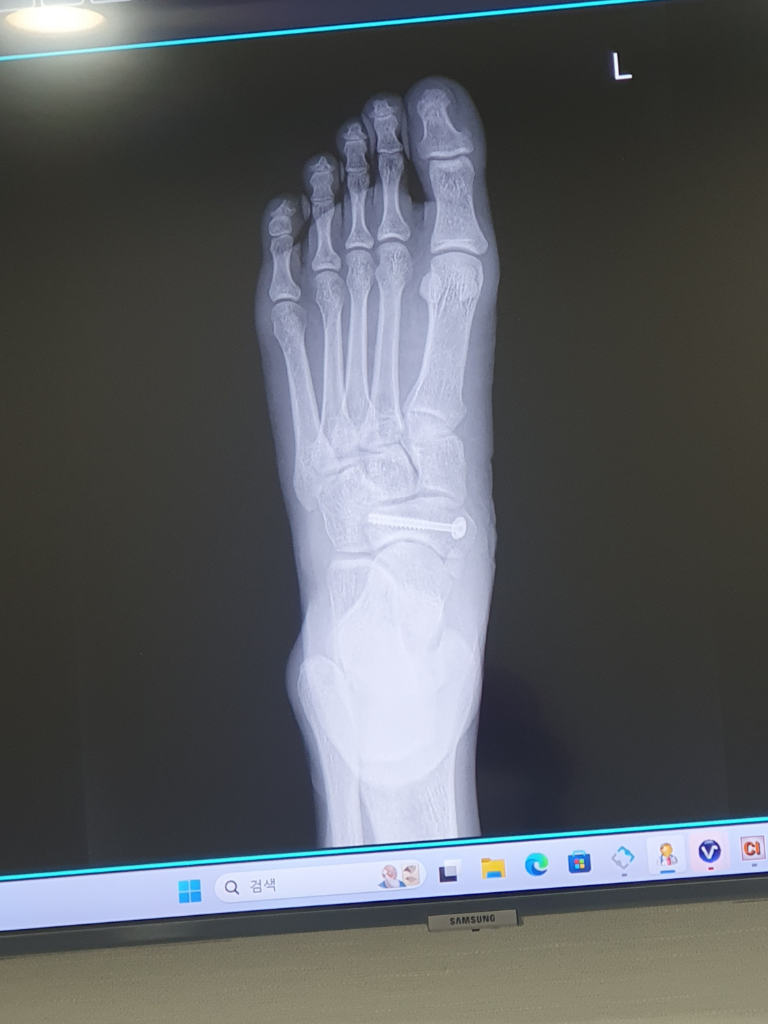

발등 골절수술을 받고 엑스레이를 찍었는데 위치가 이렇게 바뀔수있나요?

2월1일 골절로 인한 수술받았고

5일 입원하고 퇴원 후 1주일 간격으로 x-ray찍은건데

철심이 좀 더 발등뼈쪽으로 이동한게 보여집니다

• 1번 째 사진

촬영된 각도가 조금 차이가 나서 다르게 보이는 것이지 실제로 핀이 움직이지는 않았을 것이라 보입니다. 3차원 구조물을 2차원 평면에서 관찰하는 사진이므로 매번 완벽히 동일한 사진이 촬영되기는 어렵습니다.

찍는 각도에 따라 변화가 있는 것으로 보이며 철심히 더 깊이 박혔다던가 이동했을 것으로 보이지는 않습니다.